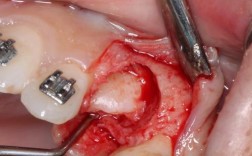

- 后果: 严重的牙根吸收会直接破坏或压迫通过根尖孔进入牙髓的血管,导致牙髓缺血坏死,吸收程度越深,坏死风险越高。

- 牙龈肿胀或瘘管: 根尖周炎的表现(坏死牙髓感染扩散到根尖周组织)。